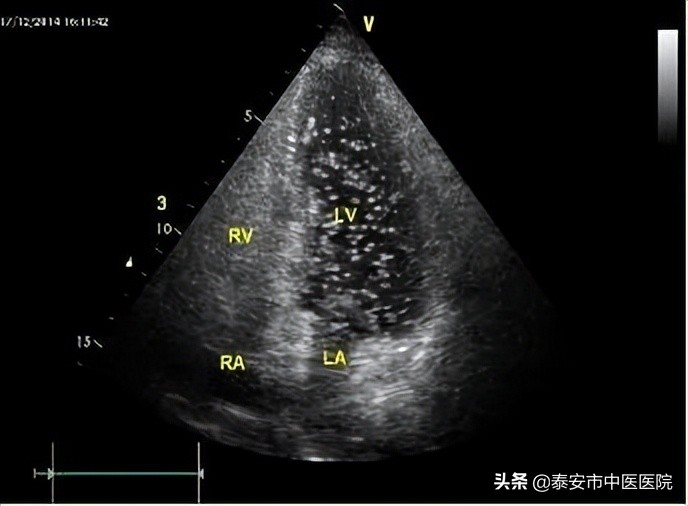

51岁的董女士,血压血糖血脂都正常,但多次突发脑梗。为什么会突然脑梗呢?为进一步明确病因,经心内科、脑内科、超声科多学科会诊,决定由超声科团队为董女士做右心声学造影,结果显示患者心脏心房水平大量右向左分流,原来脑梗塞的根源居然是卵圆孔未闭!

右心声学造影是一种无创、无辐射、简便有效的造影技术,经肘静脉注入一定量的造影剂(生理盐水与空气形成的微泡),由于微泡与血液间存在明显的声阻抗差,即使个别微泡也能清晰显示,根据显影的顺序、途径和时间,对某些结构和血流异常进行诊断和鉴别诊断。临床上主要应用于反复发作不明原因的偏头痛、短暂性脑缺血发作晕厥、无高危因素的缺血性脑卒中患者等人群,筛查是否存在卵圆孔未闭、房间隔缺损。该检查操作方便,过程简单、安全,10分钟左右即可完成。